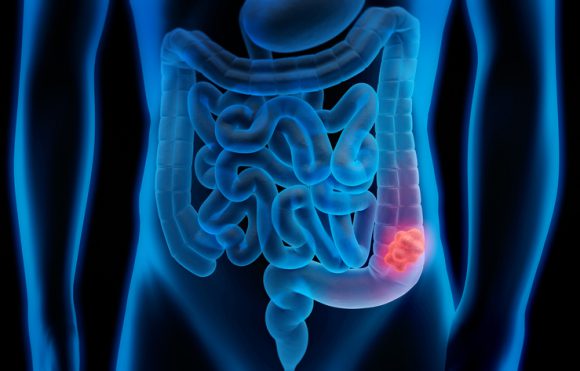

대장암은 신체 소화 기관의 마지막 부분인 대장에 발생하는 악성 종양을 가리킵니다. 대장은 결장과 직장으로 나뉘어 있는데요. 결장에 생기는 암을 결장암이라고 하고, 직장에 생기는 암을 직장암이라고 합니다. 이번에는 대장암 초기 증상에 어떤 것이 있는지 원인과 증상에 대해 살펴볼게요.